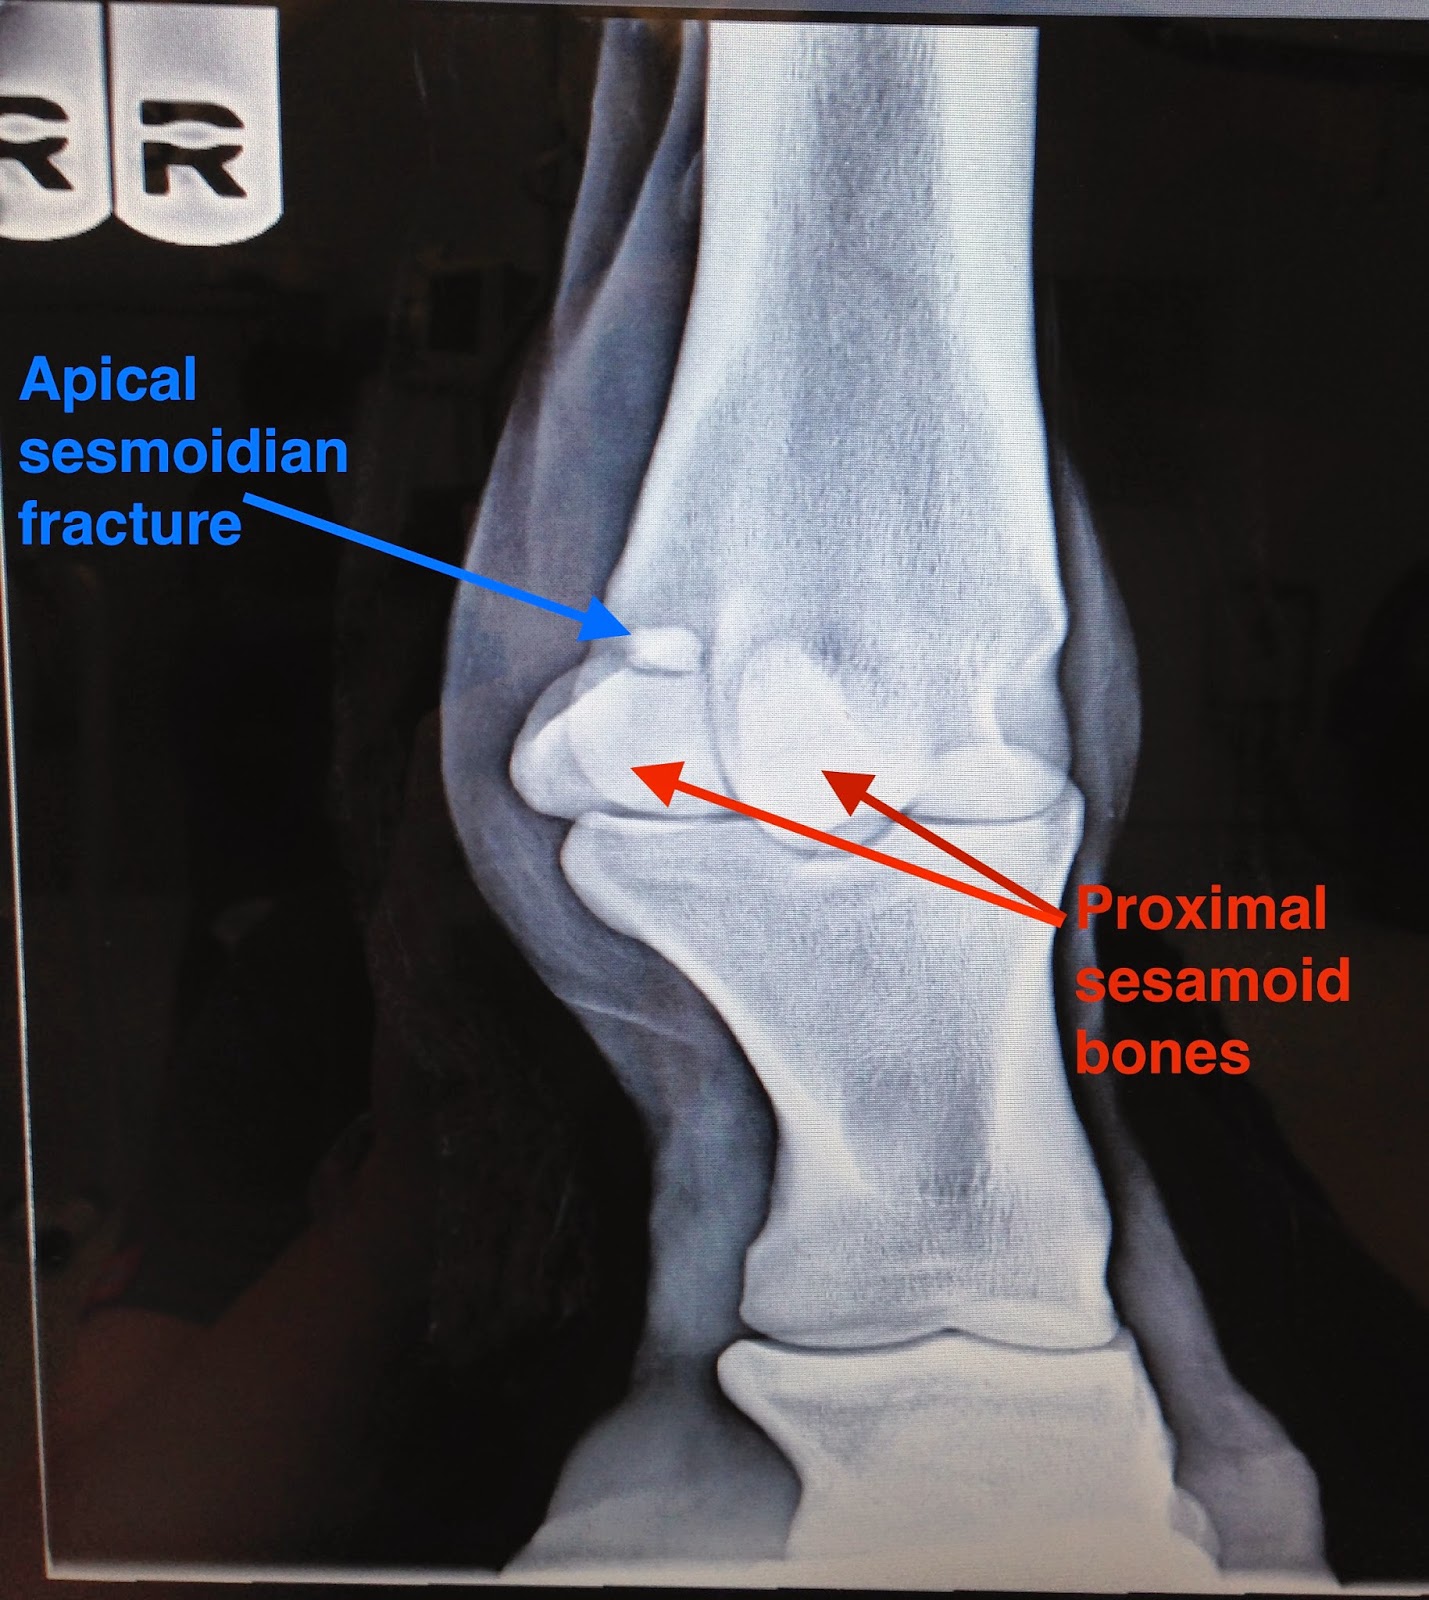

Proximal sesamoid bones: Comminuted fractures

Proximal sesamoid bones: Comminuted fractures from resources.aofoundation.org

Sesamoid fracture and injuries treated by top foot surgeons in baltimore. Symptomatic sesamoid bone fracture, fracture nonunion, or congenital bipartite sesamoid bone the medial and lateral sesamoid bones act as pulleys for the flexor hallucis brevis tendons and help. There are several ligaments attached to the sesamoids and can result in injury to the sesamoid bone.

Dr richard blake discusses the first 3 months of treatment for a sesamoid fracture under the big toe joint. Sesamoiditis is inflammation of the sesamoid bones. The tibial sesamoid is fractured much more often than the fibular sesamoid because it bears the majority of axial loading. They put me in a boot and sent me on my way to come. There are normally two sesamoid bones on each foot; A total of 24 patients with 24 sesamoid fractures that failed to respond to nonoperative measures were treated surgically with. Márcio luís duarte., et al. Sesamoid fractures most commonly refer to the bones located under the big toe. Acute fracture of the fibular sesamoid in a young athlete. Sesamoiditis and sesamoid fractures are most frequently treated without surgery. Fracture usually found on xray. Sesamoid bones perform a crucial role in the function of the rst metatarsophalangeal joint. There are several different conditions or injuries that can cause pain in the sesamoid bones of the big toe. There are several ligaments attached to the sesamoids and can result in injury to the sesamoid bone. Acute sesamoid fractures acute fractures occur as a result of an injury. Sometimes sesamoids can be bipartite, which means they each comprise two separate pieces. (mri) demonstrated a fracture of the medial sesamoid with slight edema in both feet (figures 1 and 2).